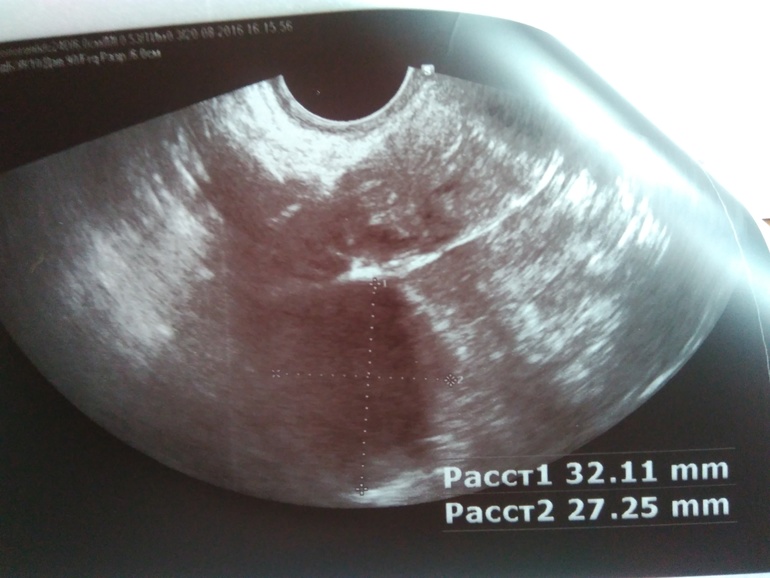

Приплыли... ДФ 32 мм😭

Первое УЗИ на 11 ДЦ - ДФ В ПЯ 15 ММ, ЭНДИК 7ММ.

Второе УЗИ на 13 ДЦ- Ф19 ММ ЭНДИК 9 ММ.

Плюс на 12 ДЦ поймала О.

А вчера😭😭😭😭😭

И очень болел ПЯ....

А сегодня обратила внимание на ЯБ. И ГЛАВНОЕ НИЧЕГО НЕ БОЛИТ!

Добавила снимок